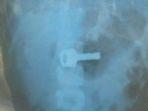

Bocah 8 Tahun Tak Sengaja Telan Kunci Gembok, Sudah Seminggu Tersangkut di Lambung, Ini Ceritanya

MZW (8), bocah di Indramayu tak sengaja menelan kunci gembok hingga tersangkut di bagian lambungnya, Rabu (14/9/2022).

Tak Sengaja Menelan, Kunci Gembok Nyangkut di Lambung Bocah Indramayu

RSUD Indramayu akan terus melajukan evaluasi memantau kondisi kesehatan bocah tersebut